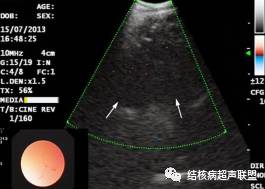

纵隔淋巴结结核好发部位多位于气管周围,尤以上纵隔气管旁淋巴结多见,其次为气管隆突下,并且常累及多组淋巴结。传统超声不能显示纵隔淋巴结,近年来气管内超声(EBUS)的应用使得超声实现了对纵隔淋巴结的扫查。微型超声探头通过气管镜进入气管支气管管腔,可清晰显示管壁各层结构及管腔外纵隔淋巴结。声像图上表现为沿气管走形的多发低回声,形态多呈类圆形,最大长径多大于10mm常相互融合,多数回声不均匀,常见粗大强回声

EBUS显示气管外侧的多个肿大淋巴结呈低回声(箭头),边界欠清,似有融合,内回声不均匀;